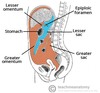

Where does the Upper GI tract end?

Duodenum